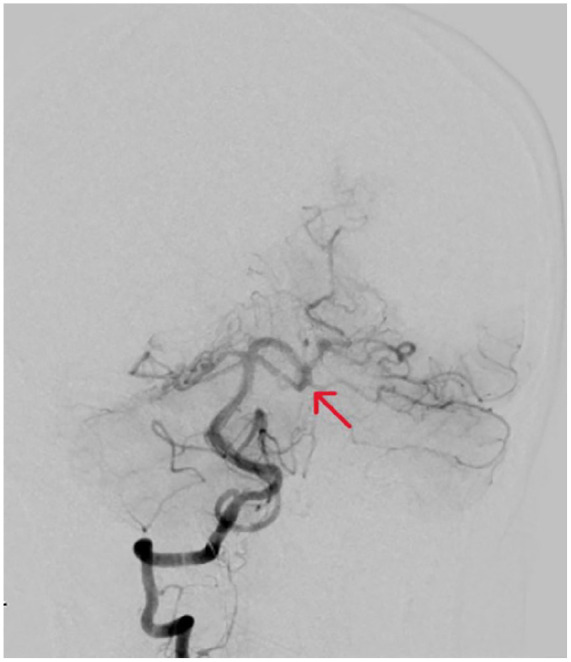

继发性嗜酸性粒细胞增多症最近引起了人们的关注,因为它可能导致血管病变,包括动脉瘤。本病例报告深入探讨继发性嗜酸性粒细胞增多与脑动脉瘤之间的复杂关系,这一联系在医学文献中尚未得到充分探讨。该病例以一名31岁女性为中心,她在无并发症妊娠后出现腿部疼痛、紫癜性皮疹和胃肠道症状。皮肤活检显示血管周围和间质性皮炎伴明显嗜酸性浸润,病因不明。实验室检查显示免疫球蛋白E (IgE)水平显著升高,为8400 kU/L。她的病情升级为弥漫性蛛网膜下腔出血并发现左小脑上动脉瘤。这种不寻常的表现,结合区分继发性嗜酸性粒细胞与原发性嗜酸性粒细胞疾病的挑战,提出了嗜酸性粒细胞在动脉瘤形成中的病理生理机制和临床意义的问题。我们讨论了嗜酸性粒细胞和血管损伤之间的潜在联系,并强调需要进一步研究以了解这种联系。临床上,该病例强调了考虑不明原因嗜酸性粒细胞增多症患者血管并发症的重要性。分享这些病例有助于在未来类似的演讲中更有见地和细致入微的方法,指导诊断和治疗策略。

Secondary eosinophilia has recently gained attention as a potential contributor to vascular pathologies, including aneurysms. This case report delves into the intricate relationship between secondary eosinophilia and cerebral aneurysms, a connection yet to be fully explored in medical literature. The case centers on a 31-year-old female who presented with leg pain, a purpuric rash, and gastrointestinal symptoms following an uncomplicated pregnancy. The skin biopsy revealed perivascular and interstitial dermatitis with a significant eosinophilic infiltration of unclear etiology. Laboratory investigations showed a markedly elevated immunoglobulin E (IgE) level at 8400 kU/L. Her condition escalated to a diffuse subarachnoid hemorrhage and the discovery of a left superior cerebellar artery aneurysm. This unusual presentation, combined with the challenge of differentiating secondary eosinophilia from primary eosinophilic disorders, raises questions about the pathophysiological mechanisms and clinical implications of eosinophils in aneurysm formation. We discuss the potential link between eosinophils and vascular damage and emphasize the need for further research in understanding this association. Clinically, this case underscores the importance of considering vascular complications in patients with unexplained eosinophilia. Sharing such cases contributes to a more informed and nuanced approach to similar future presentations, guiding diagnostic and therapeutic strategies.